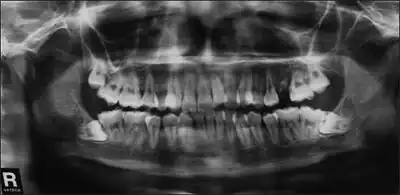

- Autosomal dominant Hyper-IgE Syndrome caused by STAT3 defects, called Job Syndrome, have characteristic facial, dental, and skeletal abnormalities. Patients with STAT3 HIES may have either delay of or failure in shedding of primary teeth. The characteristic facial features are usually set by age 16. These include facial asymmetry, a prominent forehead, deep-set eyes, a broad nasal bridge, a wide, fleshy nasal tip, and mild prognathism. Additionally, facial skin is rough with prominent pores. Finally, some patients with STAT3 HIES have scoliosis, as well as bones that fracture easily.[2]

Many patients with autosomal dominant STAT3 hyper-IgE syndrome have characteristic facial and dental abnormalities, fail to lose their primary teeth, and have two sets of teeth simultaneously.

- STAT3 may present as HIES with characteristic facial, dental, and skeletal abnormalities[9] that has been called Job's Syndrome. A common mnemonic used to remember the symptoms is FATED: coarse or leonine facies, cold staph abscesses, retained primary teeth, increased IgE, and dermatologic problems [eczema]. The disease was linked to mutations in the STAT3 gene after cytokine profiles indicated alterations in the STAT3 pathway.[10]